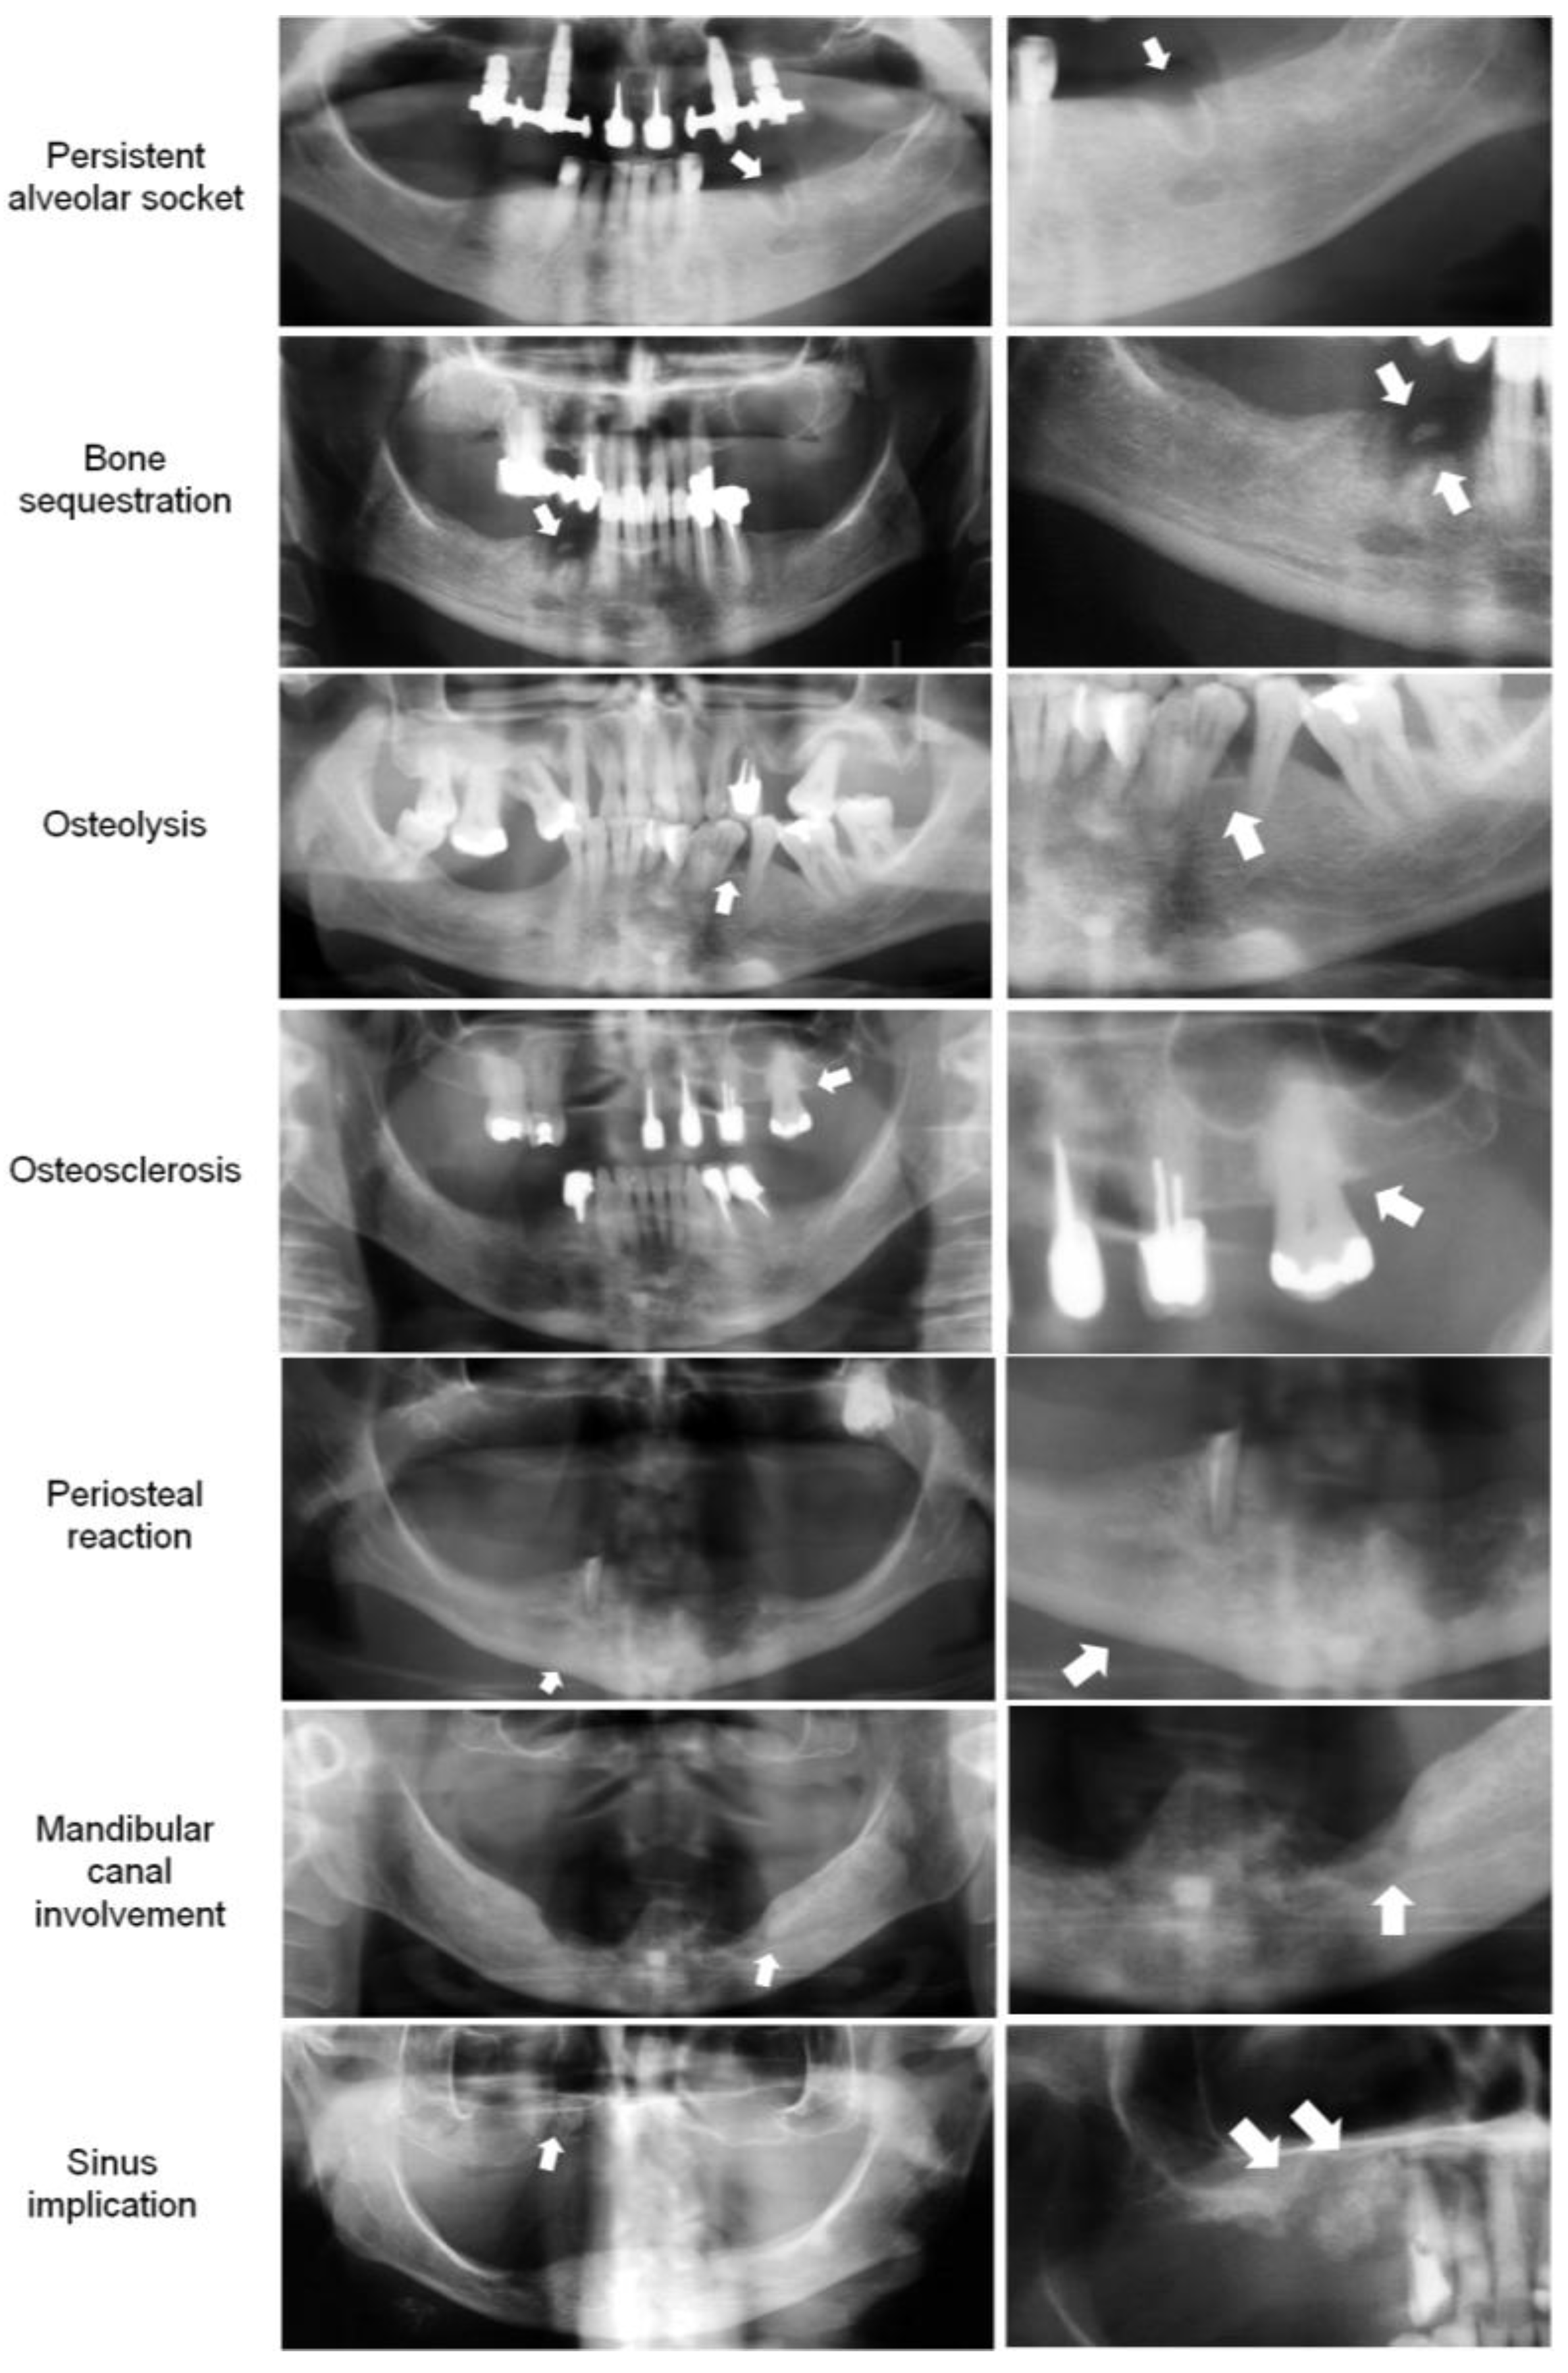

3.3.1. Bone Features on Panoramic Radiography (PAN)

3.3.2. Bone Features on Cone Beam Computerized Tomography (CBCT)